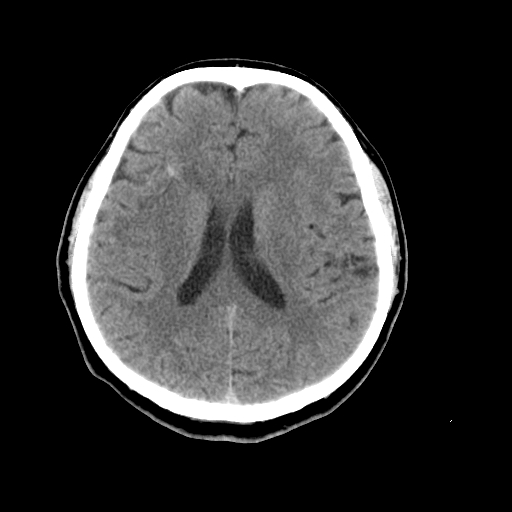

以下是引用liuyue在2008-4-28 13:34:00的发言:[br]右额叶条状高密度影,边缘清楚,周围未见水肿及占位.[br]考虑:血管畸形可能性大.[br]建议:强化ct扫描或mri检查.除外脑回钙化.

以下是引用论黑辩白在2008-4-28 12:53:00的发言:[br]右额叶局限性脑萎缩,右额叶见条状高密度影,建议mri进一步检查。[br][br][本贴已被 论黑辩白 于 2008-4-28 13:08:16 修改过]